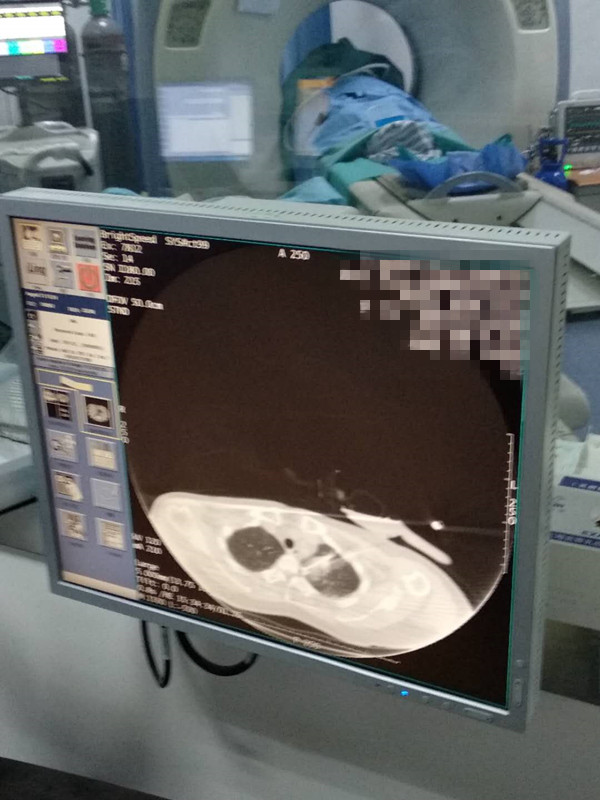

50岁肺部氩氦刀冷冻消融

发布人:美国氩氦刀技术官方网站    发布时间:2020/8/17 16:21:20